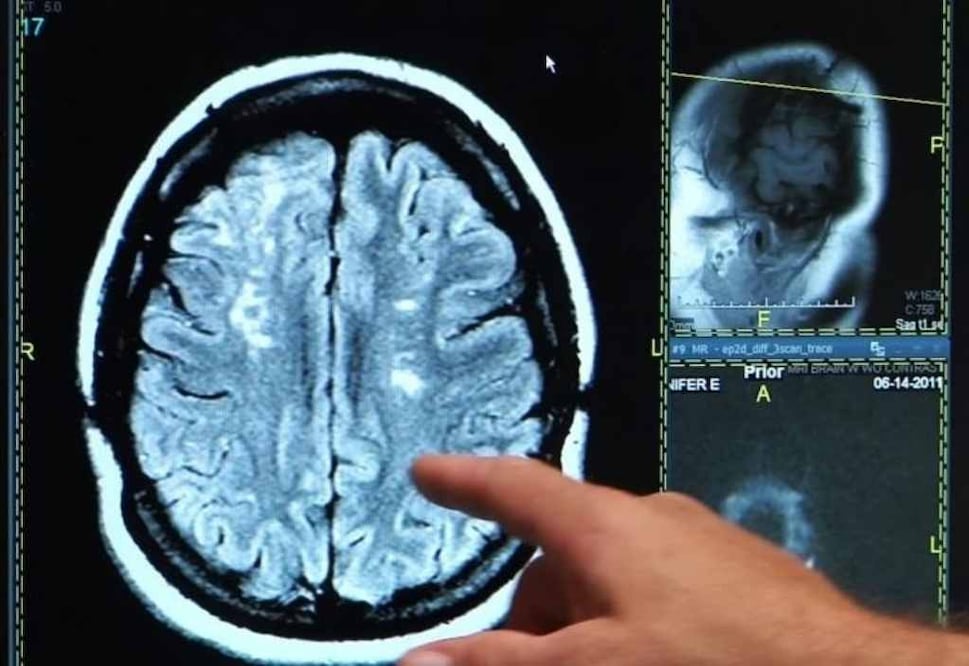

Los nacidos entre 1945 y 1954 pueden ser considerados la "generación más sana en cuanto a accidentes cerebrovasculares", según un estudio realizado por la Universidad de Rutgers, en Nueya Jersey, Estados Unidos, que encontró la incidencia más baja de ictus isquémico en este grupo de edad en los últimos 20 años.

Por el contrario, la tasa de accidente cerebrovascular es más del doble en la generación X, es decir, las personas nacidas entre 1965 y 1974, durante el mismo periodo de tiempo.

"La incidencia de accidente cerebrovascular ha disminuido considerablemente en general desde 1950, debido al avance de la medicina", afirma Joel N. Swerdel, autor principal del estudio realizado en el Instituto Cardiovascular de Nueva Jersey en la Escuela de Medicina de la Universidad de Rutgers ."Sin embargo, encontramos que la tendencia se invierte en las generaciones más jóvenes donde la obesidad y la diabetes están probablemente causando un aumento en las enfermedades cardiovasculares", añade.

Los investigadores analizaron más de 225.000 registros de datos de accidente cerebrovascular entre 1995 y 2014, separados en cinco grupos, cada uno con una edad de 10 años. El análisis, que se publica en 'Journal of the American Heart Association', encontró que las personas nacidas en los 20 años previos a 1945 y los nacidos en los 20 años posteriores a 1954 tenían mayores riesgos de accidente cerebrovascular. Sólo el grupo que ahora está entre 60 y 70 años de edad vio una reducción en la incidencia de accidente cerebrovascular durante el intervalo de años incluidos en el estudio.

"Una mayor incidencia de ictus en individuos nacidos antes de 1945 no fue sorprendente, ya que no se beneficiaron de la disponibilidad de fármacos hipolipemiantes, como las estatinas, y la terapia antihipertensiva, al igual que las generaciones más jóvenes", apunta Kostis, investigador principal del trabajo. "Sin embargo, la creciente incidencia del accidente cerebrovascular en la generación más joven --los que están entre las edades de 35 y 50 años-- es alarmante y merece más investigación".

Los investigadores atribuyen a varios factores la tendencia al alza, como la falta de adherencia al tratamiento prescrito, por ejemplo tomar medicamentos para controlar la presión arterial, y un incremento significativo en la obesidad y la prevalencia de la diabetes, ambos factores de riesgo de la enfermedad cardiovascular. Aunque MIDAS incluye datos de Nueva Jersey, los investigadores creen que la evidencia es indicativa de las tendencias en Estados Unidos.